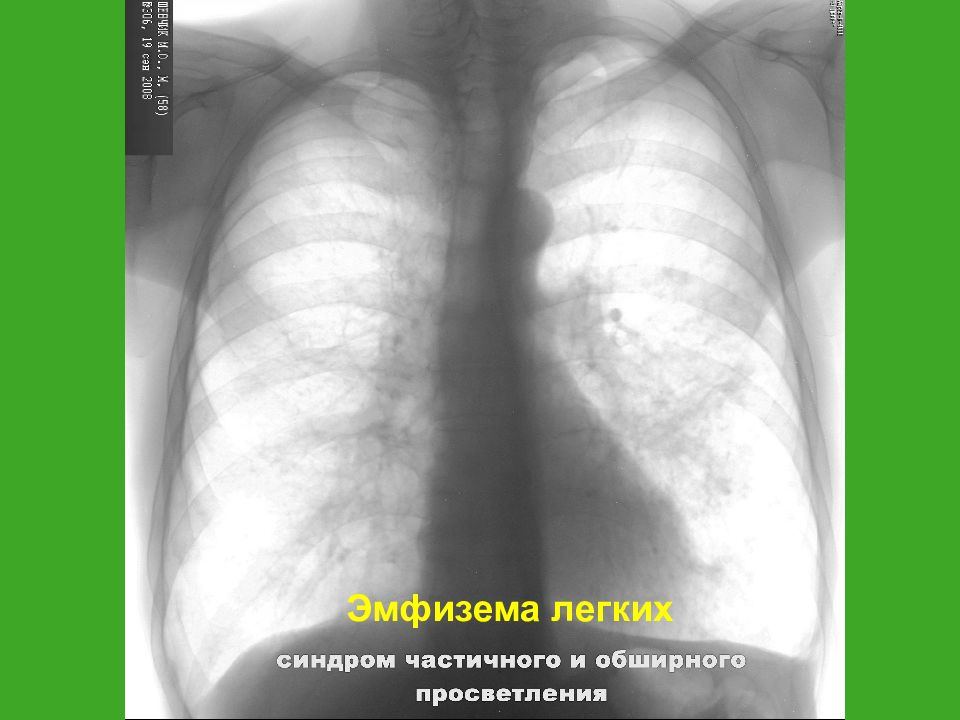

Рентгенологические изображения и синдромы патологии легких

Раздел: Кадры-подсказки